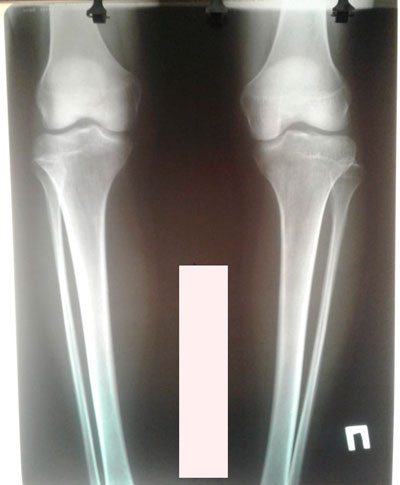

Дата операции - 20.06.2019г.

Исходник - 27 лет.

Ротация с обеих сторон.

Правая голень заметно тоньше, ратированее и деформированее.

Ножки и рентген перед снятием аппаратов.

Дата снятия аппаратов - 17.09.2019.

Срок сращения - 87 дней.